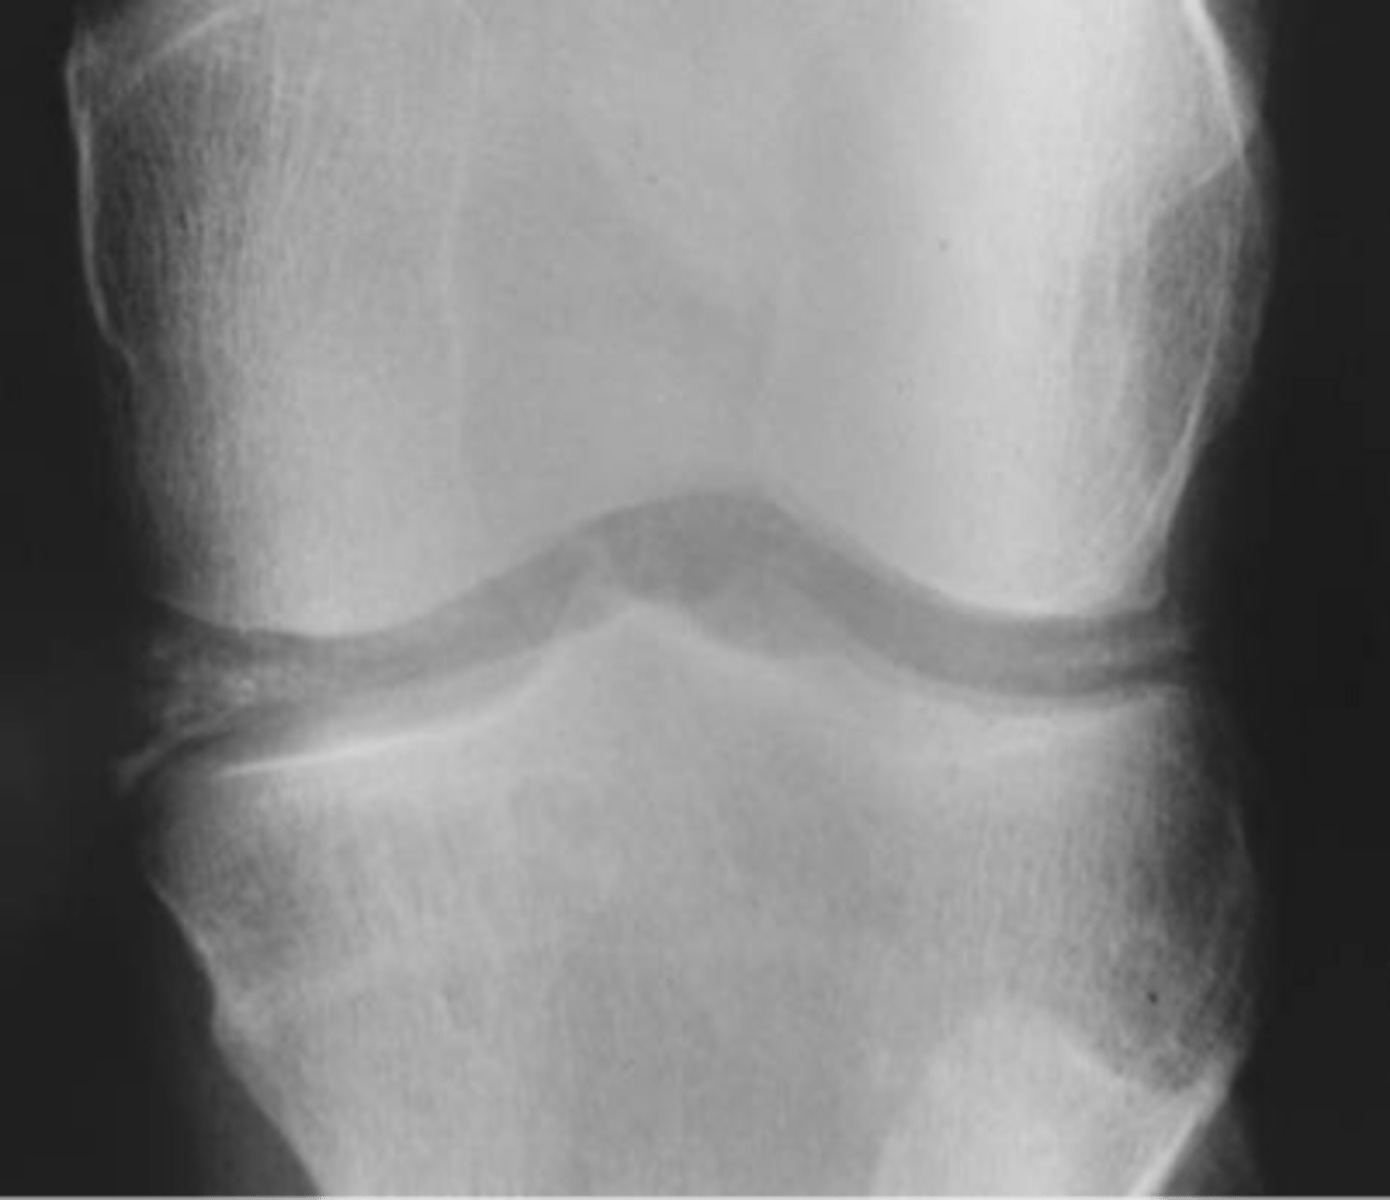

- Soft tissue swelling

- Chondrocalcinosis

- Severe degeneration

- Pyrophosphate arthropathy

- Articular destruction